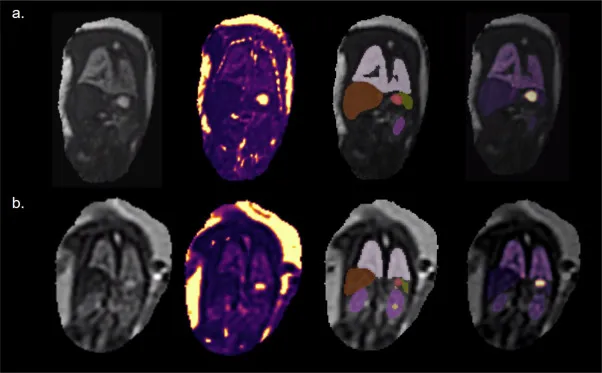

图6.从左到右:第二个回波的胎儿可变形切片到体素重建(dSVR)示例;T2*图dSVR(使用“地狱”色图显示,从深蓝色(0 ms)到亮黄色(1000 ms));多通道网络生成的标签图;叠加在第二个回波3D体积重建上的器官T2*图。上排:胎龄35.71周,下排:胎龄23.14周。